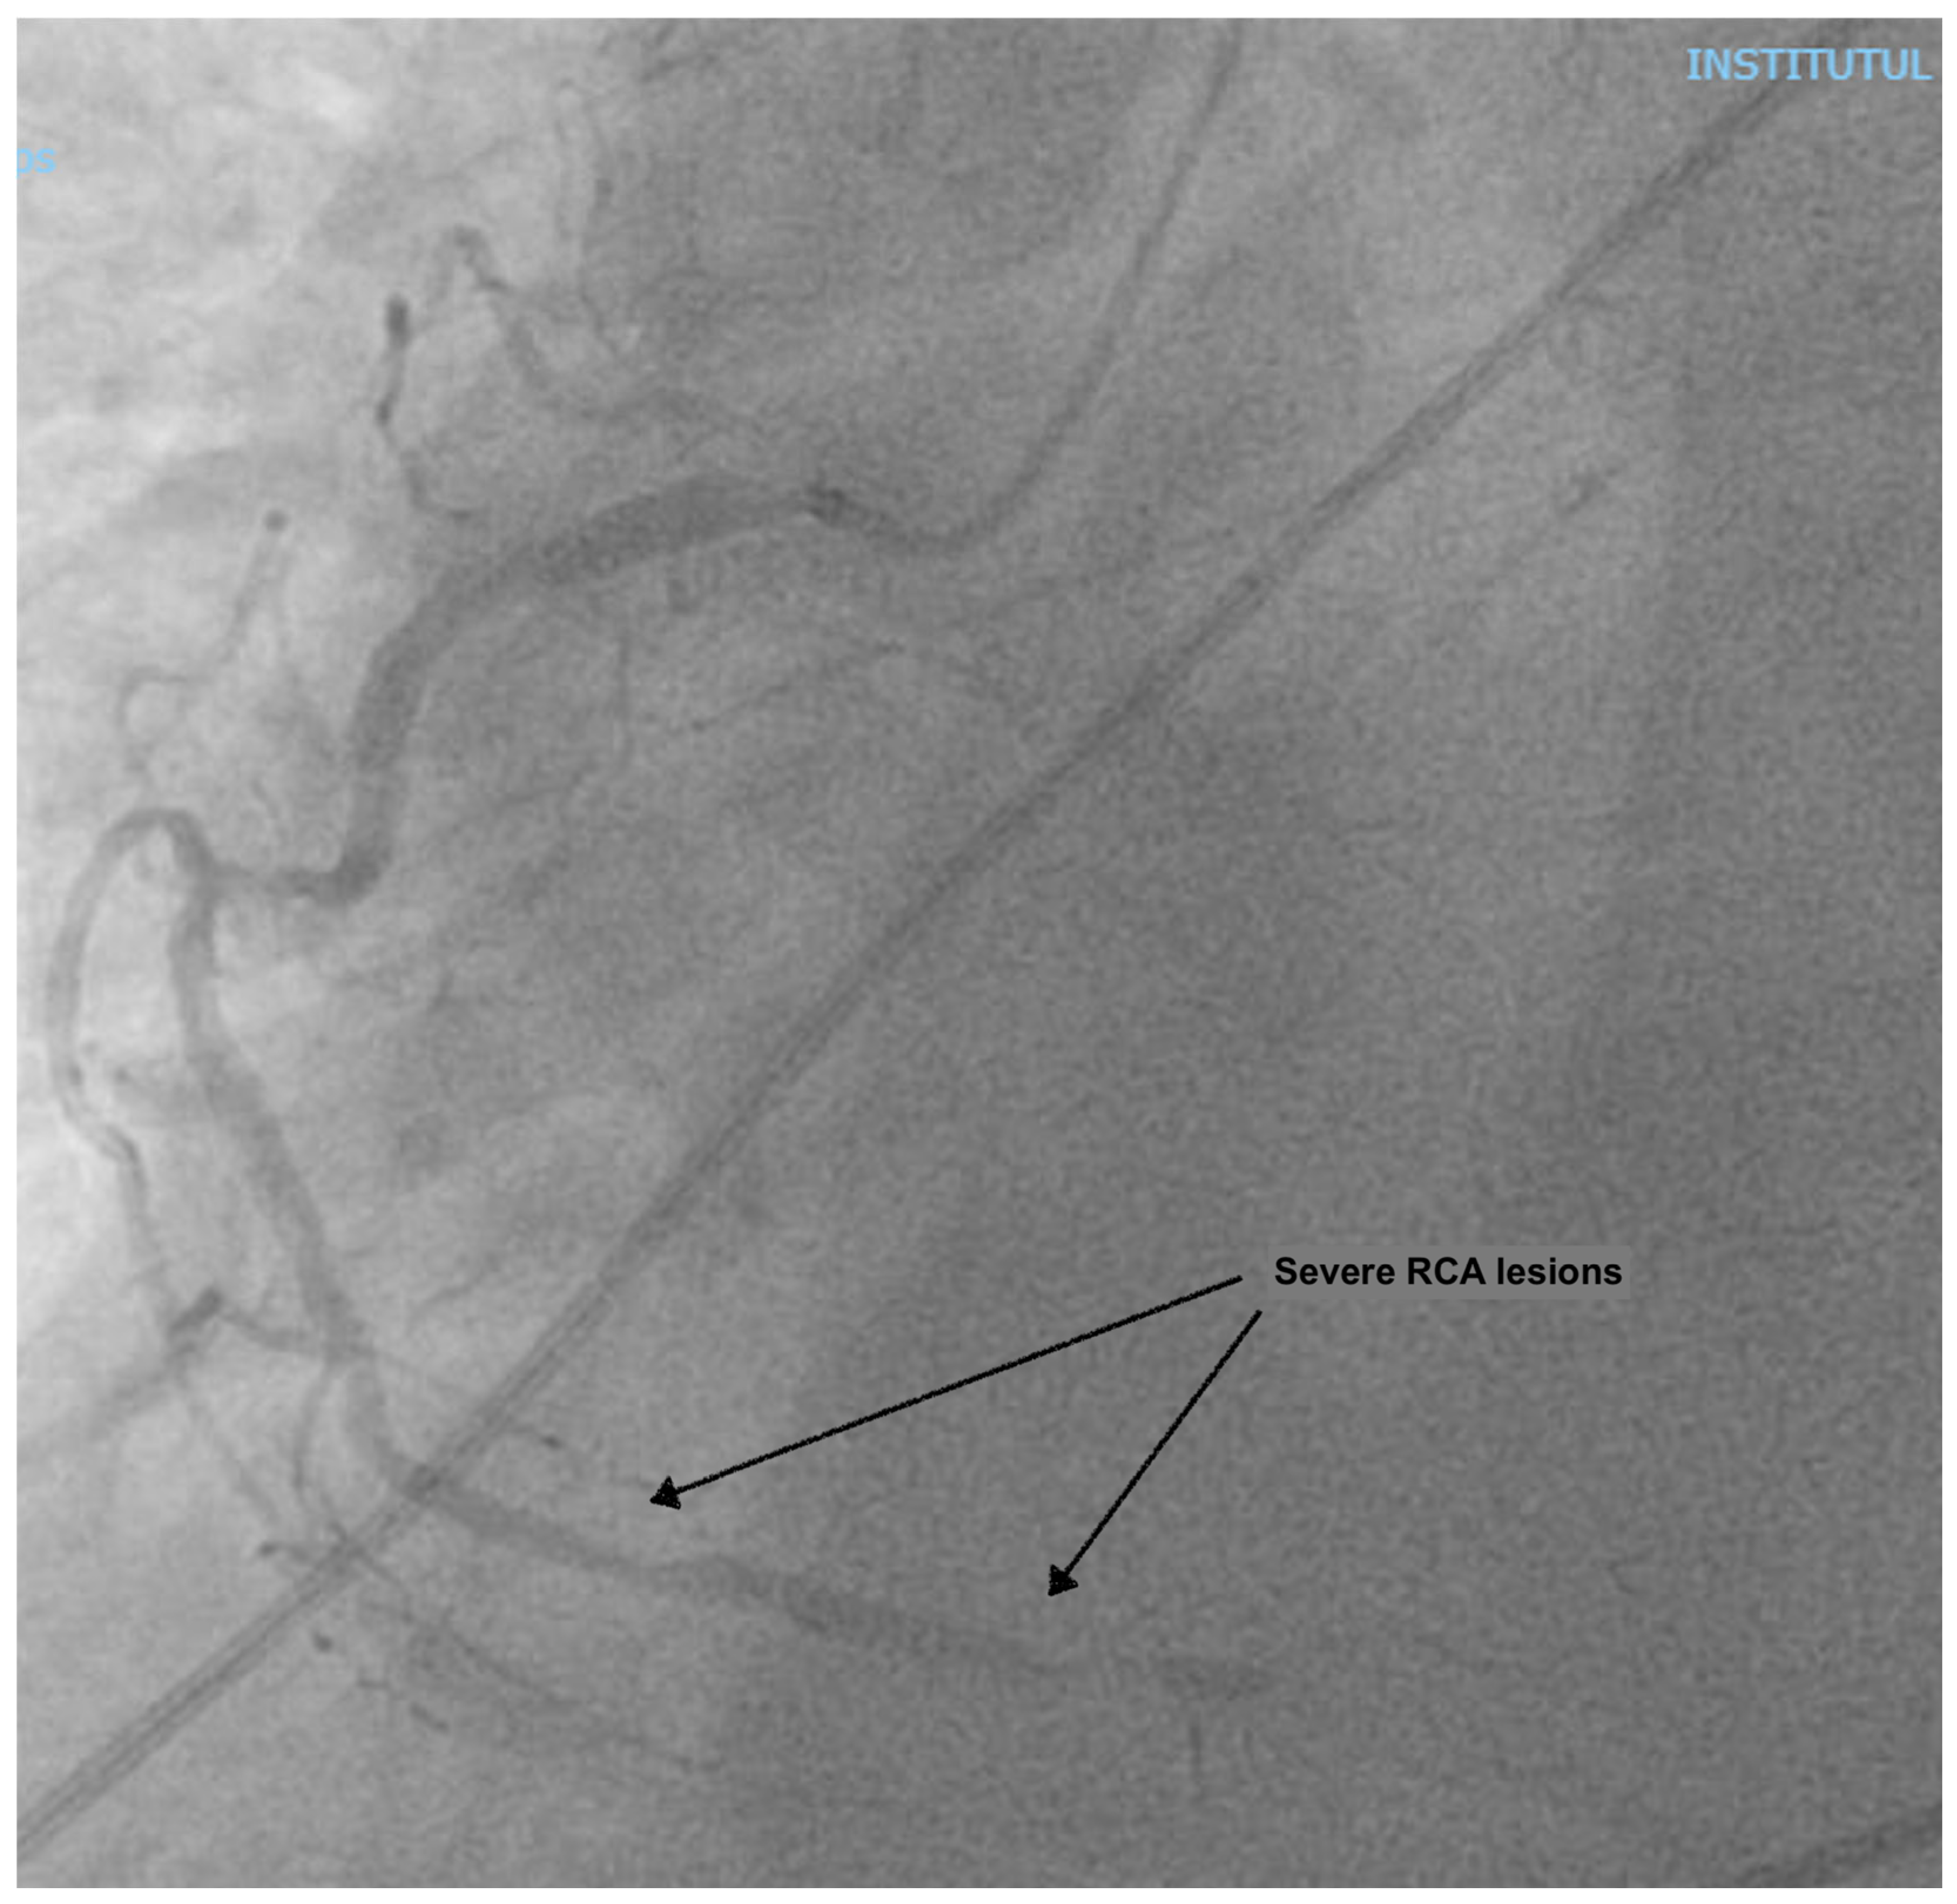

At presentation, the patient was in cardiogenic shock, at Society for Cardiovascular Angiography and Interventions (SCAI) stage C, with acute pulmonary edema: he was dyspneic, with a breathing rate of 25/min; an SpO2 of 90% under 6 L/min of oxygen, with diffuse fine crackles in both lungs; a blood pressure (BP) of 120/80 mmHg; a heart rate of (HR) 120/min; warm, but clammy skin; and a serum lactate of 2.5 mmol/L. He had a loud holosystolic murmur at cardiac auscultation. The ECG showed inferior ST-elevation myocardial infarction (STEMI), and the fast trans-thoracic echocardiography (TTE) showed moderate left ventricular (LV) dysfunction, with an ejection fraction (EF) of 40%, a moderate MR (vena contracta 6 mm), and a large VSD (2 cm), with left-to-right shunting. The patient was taken to the cardiac catheterization laboratory, where a right coronary artery (RCA) sub-occlusion was diagnosed (Figure 1), with no other hemodynamically significant coronary lesions. During the procedure, the patient was managed using non-invasive pressure-support mechanical ventilation (NIV) due to aggravated dyspnea and orthopnea. Interventional revascularization was not possible or indicated due to the distal lesions, with TIMI II flow, and the lack of benefit in an already non-viable myocardial territory. Despite significant PAD of the left inferior limb (Figure 2), an intra-aortic balloon pump (IABP) via the superficial left femoral artery was placed immediately.

Figure 1. Coronary angiography showing an RCA sub-occlusion.